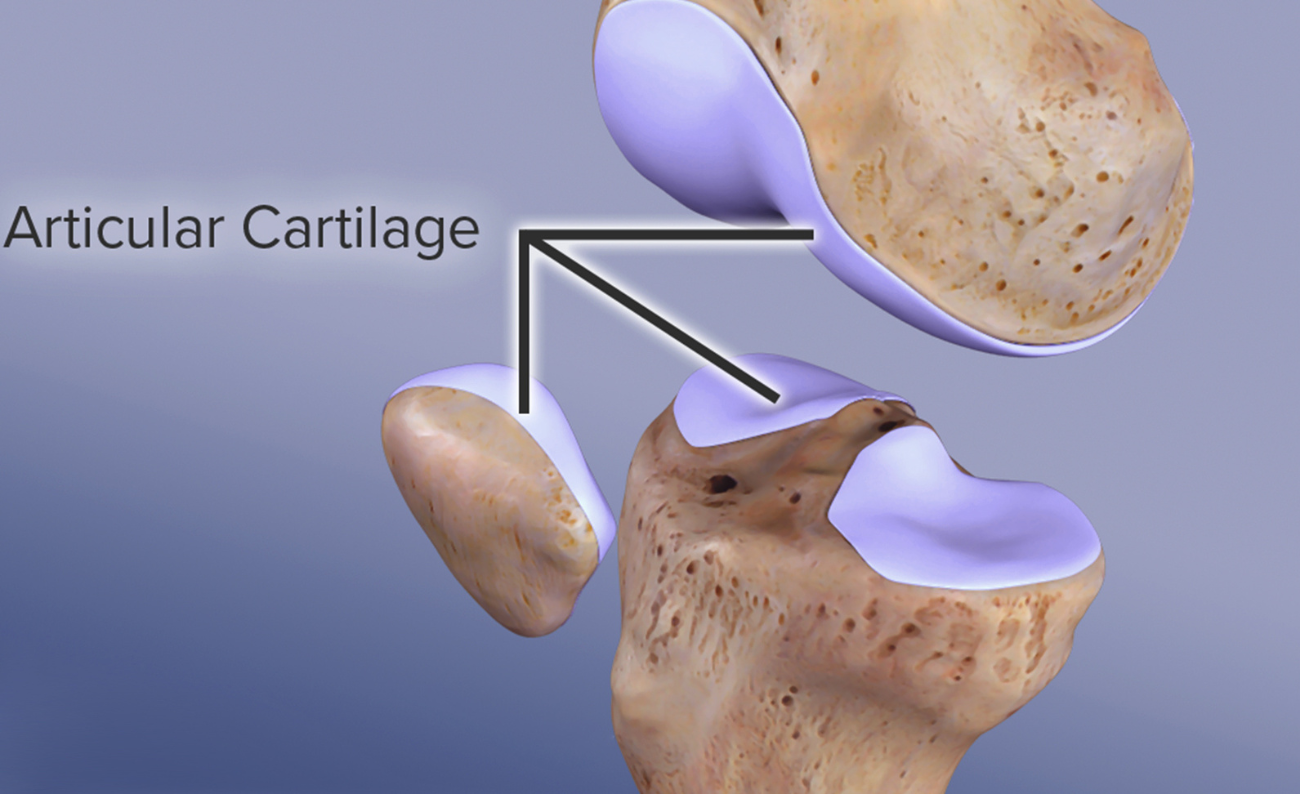

Articular Cartilage Damage

Articular Cartilage is the layer of smooth connective tissue that covers the ends of bones at every joint. This tissue is maintained and repaired on a continuous basis. It is one of the most lubricated materials on earth and has the lowest coefficient of friction,